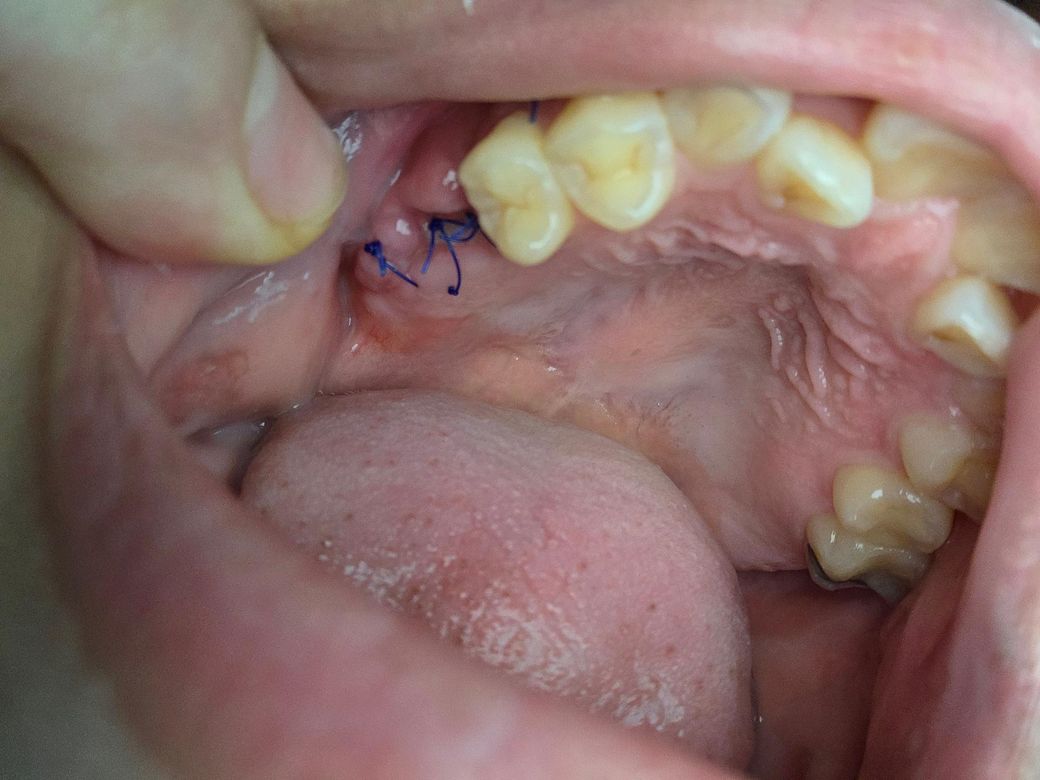

임플란트 뼈이식 시술한지 2주정도 됐습니다

고름같은게 보이고 뼛가루가 너무 많이나와서 걱정이에요 임플란트 한지 2주정도 됐습니다

다른사람들보다 뼈가 많이없어서 일반인보다 더많이 뼈를 이식했다고 했어요

• 1번 째 사진

1. 엄밀히 말하면 흰 가루는 실제 뼈(뼈가루)가 아니므로 큰 걱정은 안하셔도 됩니다.

2. 수술 후 주의사항 잘 지키면서 기다리면 됩니다.